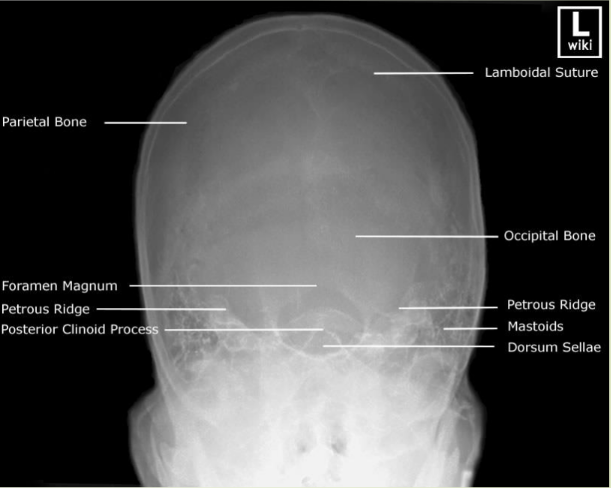

term image

knowt flashcard image